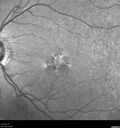

57 year old male - The right eye has more macular degeneration than the left eye. The left eye has a lot of floaters. He was noted to have macular degeneration in both eyes more in the right than the left eye. He is wondering if there is anything to do. The patient did not notice any vision change prior to June of 2022. He was then diagnosed with vitelliform macular dystrophy. The patients mother and grandmother had RP.

Pattern Dystrophy - PHPR2 Gene92 views57 year old man- VA 20/25 OD, 20/20 OS - Many family members have retinitis pigmentosa     (0 votes)